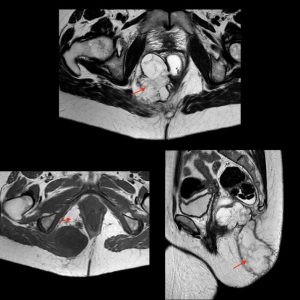

La analítica no refleja datos de infección y se realiza una ecografía endorrectal donde se objetiva una tumoración heteroecoica pararrectal derecha que se extiende hasta la rama derecha del puborrectal de 3,5×2,5 cm (ver imagen 1). Se completa estudio con resonancia magnética donde se informa una formación de 13×7,5×6,5 cm hiperintensa en T2 e hipointensa en T1 de borde lobulado y bien definido, con múltiples septos en su interior, en región pararrectal derecha ocupando la fosa isquiorrectal, con aparente comunicación con la pared lateral derecha del recto a las 8 horas a la altura del esfínter anal sin poder descartar etiología neoplásica (ver imagen 2), ni orientar más su posible naturaleza.

Imagen 2: Resonancia magnética: formación de 13×7,5×6,5 cm hiperintensa en T2 e hipointensa en T1 de borde lobulado y bien definido, con múltiples septos en su interior en región pararrectal derecha ocupando la fosa isquiorrectal, con aparente comunicación con la luz anorrectal.